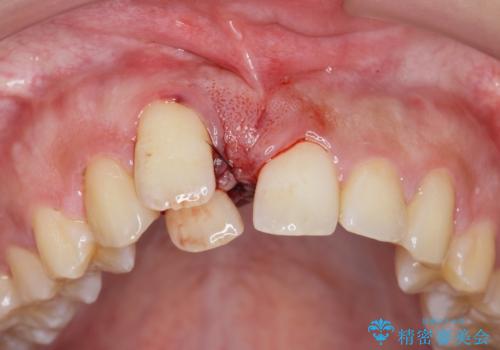

正中過剰埋伏歯で生じた前歯の審美障害 矯正治療での改善

- 前歯の見た目に悩まれて来院されました。

当初他院では、抜歯を行いセラミックブリッジを提案されていましたが、他の方法はないかと総合歯科治療を行う当院へと相談来院されました。

「時間がかかっても良いので、できれば歯を抜かずに矯正治療で治したい。」という強い希望があったので、矯正治療で歯並び・審美性の改善を計画します。

見た目、噛み合わせが大きく改善し、大変喜んでいただくことができました。